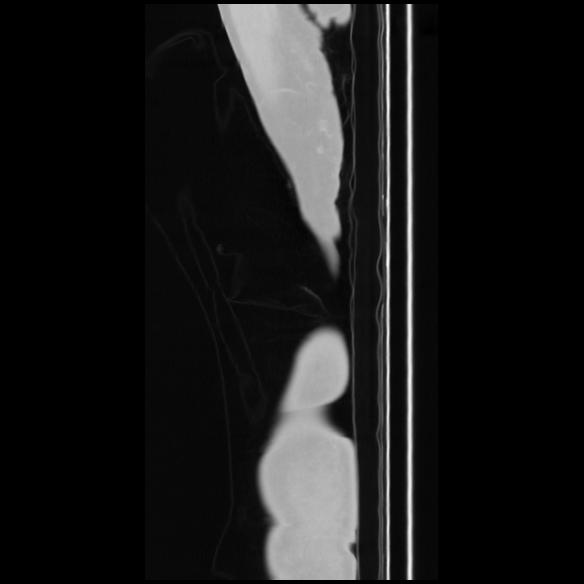

7 CUERPO,CE,Sagittal,3.000,CUERPO,Sagittal,